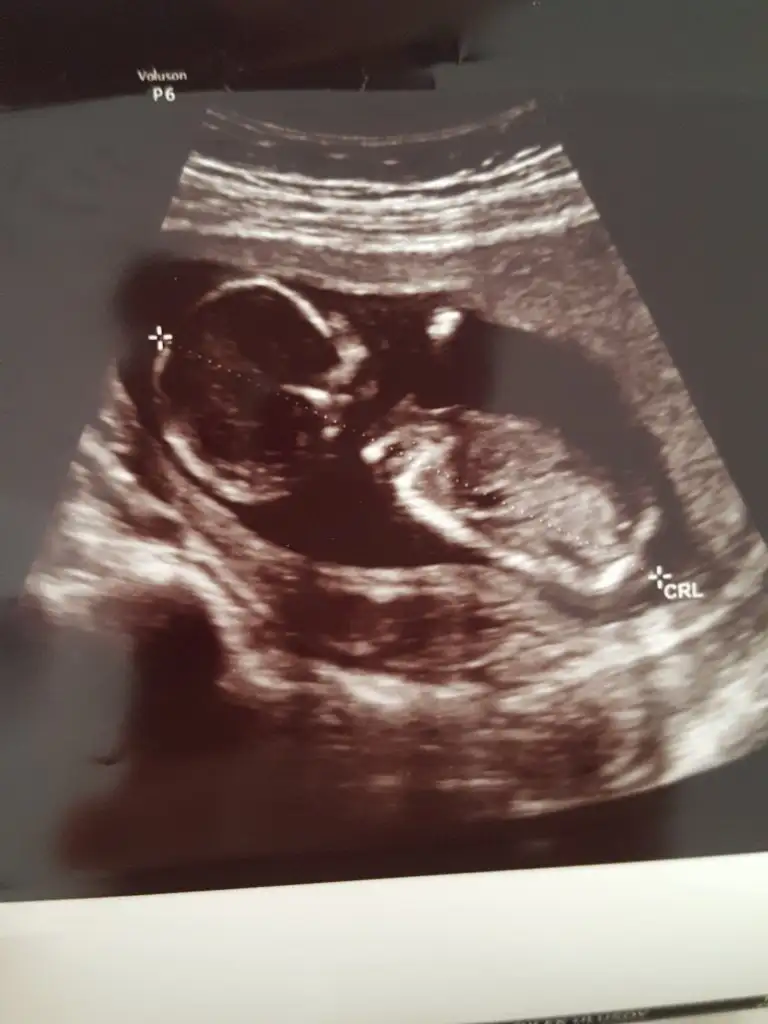

Size 15. Haftadan fotoğraf atiyorum

Bugun 14+1im güveniyorum nolurr